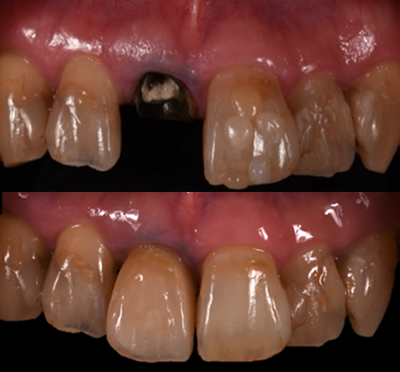

2.修復技術の革新(モノブロック修復)

象牙質・修復物を一体化させる接着を最大限活かした「モノブロックコンセプト」に基づき、残された歯根に対して、コンポジットレジンのみを用いた方法を提案しました。これにより、歯根を温存することが期待できます。特に、前歯部での適応において有用性を評価しました。